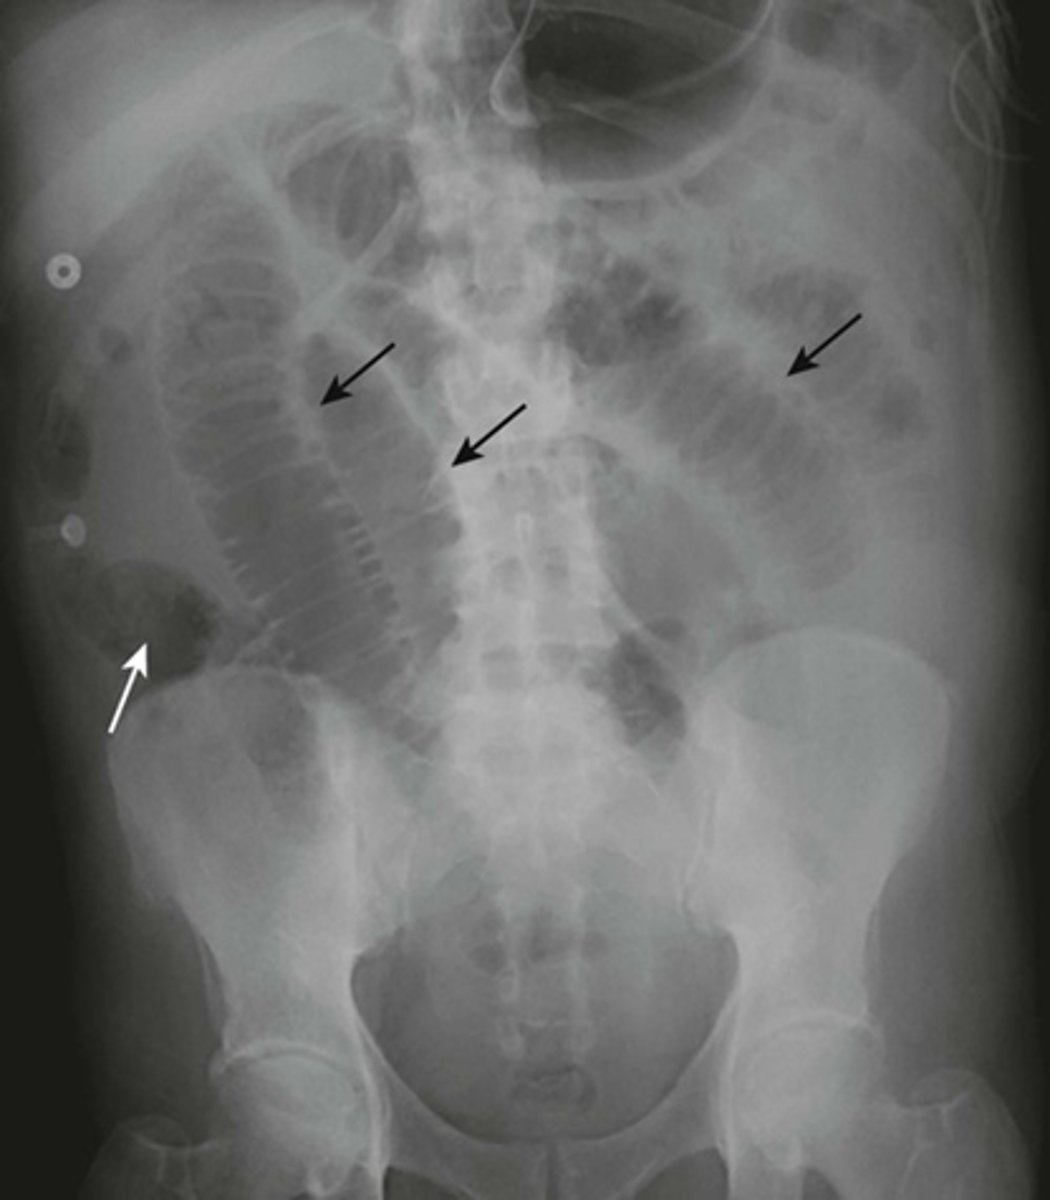

HEPATOMEGALY

BLACK ARROWS: displacement of all bowel loops from RUQ to iliac crest and across the midline.

Hepatomegaly is usually indicated by displacement of all bowel loops from RUQ to the iliac crest and across the midline, as in this pt with cirrhosis.

Sometimes the liver can be so enlarged that it will be obvious even on conventional radiographs

SPLENOMEGALY

WHITE ARROWS: spleen

BLACK ARROW: 12th posterior rib

Spleen is usually about 12 cm in length and DOES NOT project below the 12th posterior rib.

Splenomegaly can also displace the stomach bubble toward or across the midline.